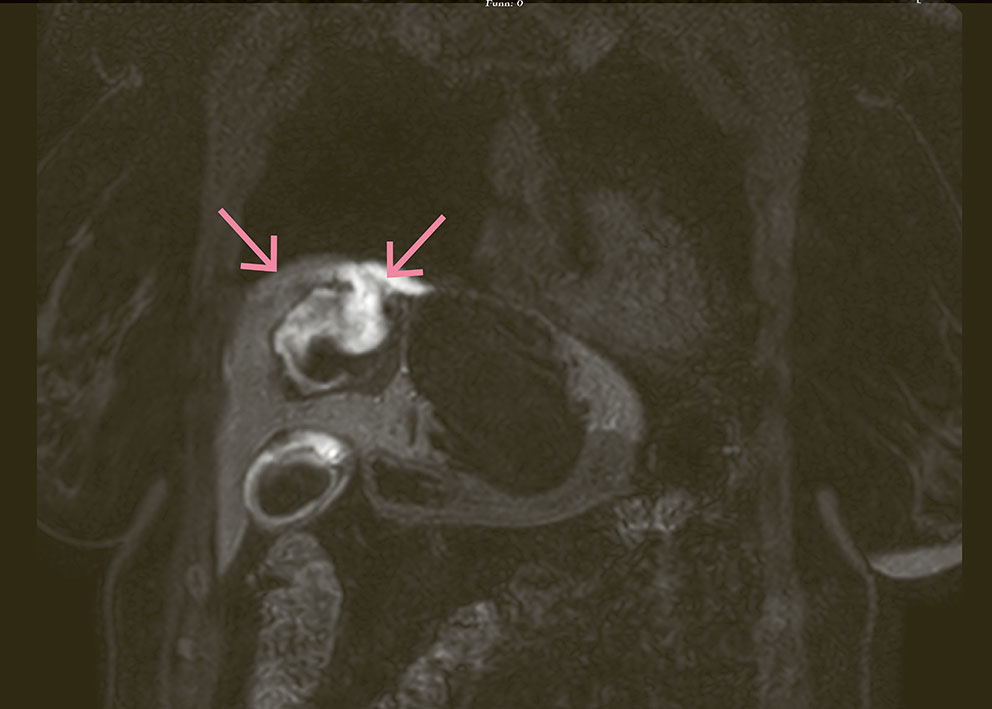

MR-bildet er tatt i koronalplan, T1 Dixon vann, hepatobiliær fase, 20 minutter etter injisering av dinatriumgadoksetat (Primovist) 1 ml/10 kg for å se etter posttraumatisk gallelekkasje hos en kvinne i 50-årene med kjent fibropolycystisk leversykdom. Cysten på bildet viser inhomogent signal forenlig med kontrast og blod. Det er ekstravasering av kontrast fra rumpert cyste med 14 mm åpning ut i perihepatisk rom og gallelekkasje til peritoneum (piler).